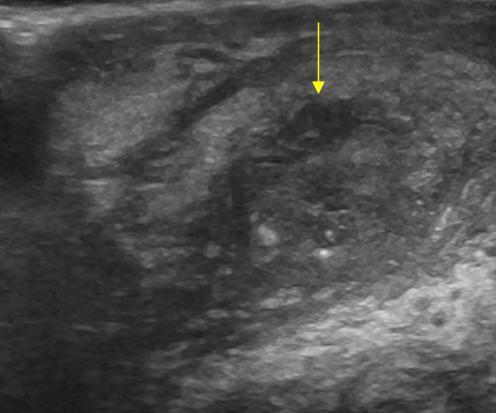

Viêm mào tinh hoàn

» Thông tin: Nam giới – 39 tuổi.

» Lâm sàng: Sưng đau vùng bìu.

# Viêm mào tinh hoàn apxe hóa.